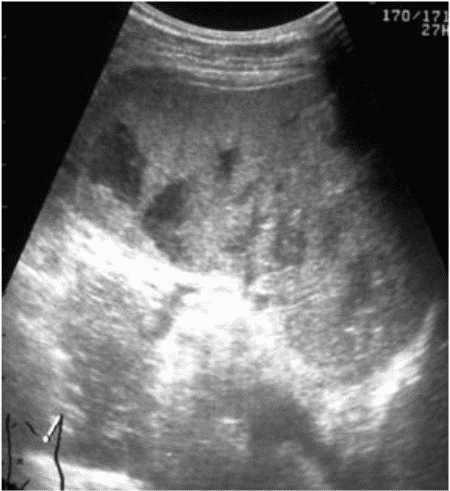

В связи с вышеизложенным особое клиническое значение приобретают косвенные эхографические признаки чрескапсульного разрыва органа, прежде всего внутрибрюшинного кровотечения, отмеченного у всех больных с таким характером травмы. Периспленическая гематома (рис. 8) представляет собой околоорганное скопление крови, полностью либо частично окружающее поврежденную селезенку и ограниченное такими анатомическими образованиями, как купол диафрагмы, задний листок париетальной брюшины, петли кишечника, фиксированные пряди большого сальника и т.д.

Рис. 8. Эхограмма чрескапсульного разрыва селезенки. Периспленическая гематома указана стрелками.